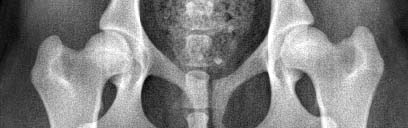

Jacko HD A und ED frei :-)